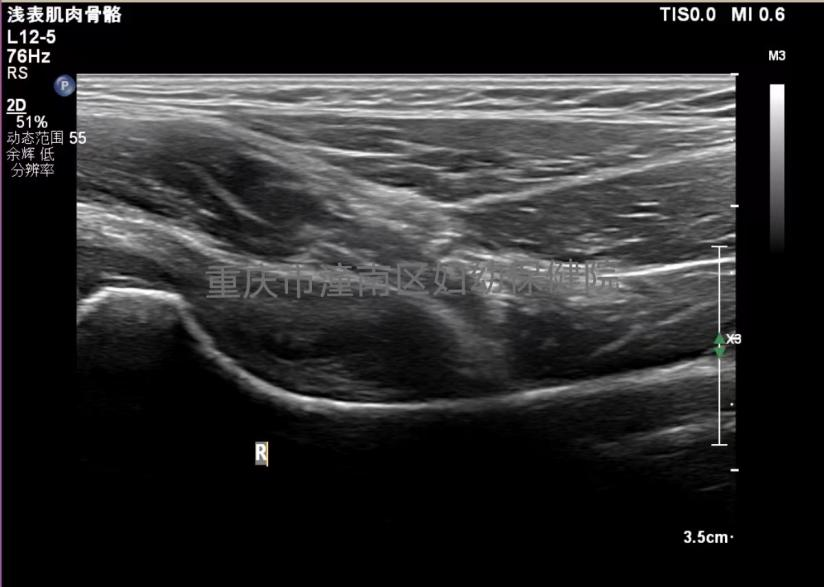

我院影像诊断科通过超声检查早期发现积液、滑膜增厚等情况,可明确诊断小儿急性髋关节滑膜炎。并且这种检查无创、快捷、无辐射。

滑膜增厚、积液